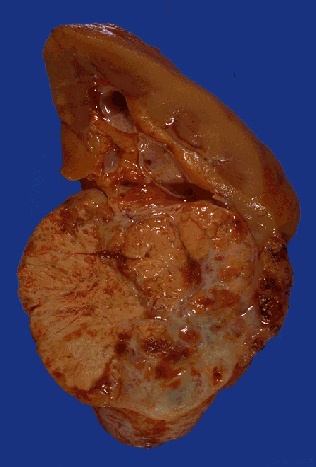

Image 5.1 A large mass involves the lower pole of the kidney and is variegated, with yellow, tan, and hemorrhagic necrotic areas seen on the cut surface. The tumor in this case did invade the renal capsule but did not involve the renal vein.